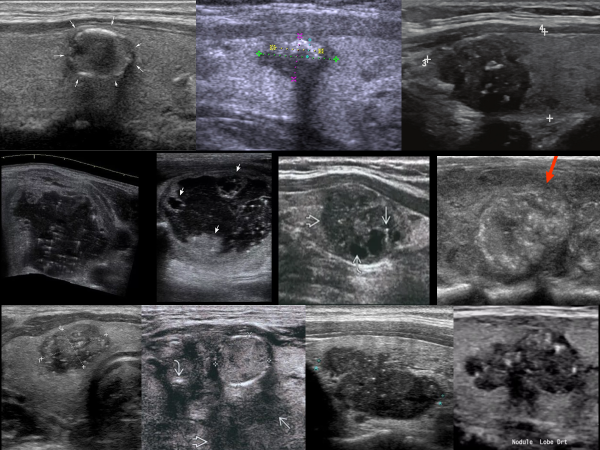

Гиперэхогенные включения новообразований щитовидной железы

При УЗИ гиперэхогенные включения новообразований щитовидной железы визуализируются как точечные, линейные или объемные структуры высокой эхогенности, в ряде случаев с акустической тенью. Традиционная трактовка гиперэхогенных включений - «кальцификаты», которые подразделяют на «микрокальцинаты», соответствующие точечным, менее 1 мм, гиперэхогенным частицам без акустической тени, и «макрокальцификаты» - гиперэхогенные участки более 1 мм, имеющие акустическую тень; также может быть кальцинированный узел и кальцинированная капсула узла. Кальцификаты (кальцинаты) представляют собой скопления солей кальция и возникают на месте разрушения ткани, либо вследствие нарушения регуляции гомеостаза. Гиперэхогенные включения значительно чаще наблюдаются в злокачественных узлах (75%), чем в доброкачественных (5%); наличие в узле «микрокальцификатов» расценивается как вероятный признак его злокачественности. Морфологически в злокачественных опухолях выявляются 3 типа структур: В доброкачественных узлах

Гиперэхогенные включения значительно чаще наблюдаются в злокачественных узлах (75%), чем в доброкачественных (5%); наличие в узле «микрокальцификатов» расценивается как вероятный признак его злокачественности.

Морфологически в злокачественных опухолях выявляются 3 типа структур:

• Псаммомные тельца (50%);

• Кальцификаты (30%);

• Участки склероза (около 70% - наиболее часто).

В доброкачественных узлах псаммомные тельца морфологически не определяются; в редких случаях наблюдаются кальцификаты (5%); наиболее часто также выявляются участки склероза (более 60%).

В соответствии с УЗ-характеристиками и морфологическим содержанием, гиперэхогенные структуры новообразований ЩЖ выделяют 3 варианта:

• Яркие точечные гиперэхогенные включения;

• Объемные гиперэхогенные включения без акустической тени;

• Объемные гиперэхогенные включения с акустической тенью.

Яркие точечные гиперэхогенные включения являются преимущественным ультразвуковым признаком псаммомных телец, реже мелких кальцификатов.

Псаммомные тельца (от греч. psammos - песок) представляют собой особую разновидность кальцификатов, имеют характерную слоистую концентрическую структуру и характерны для папиллярных карцином (65-80%). Псаммомные тельца можно обнаружить в строме опухоли и окружающей ткани ЩЖ, в лимфатических капиллярах, а также в метастазах папиллярной карциномы в лимфоузлы. По мнению большинства исследователей, они образуются на месте разрушения папилл, в силу чего их нередко именуют «надгробными камнями» погибших папилл. Псаммомные тельца не следует путать с кальцификатами, которые наблюдаются при любой тиреоидной патологии, а не только при папиллярной карциноме.

При УЗИ псаммомные тельца визуализируются как множественные, очень яркие, точечные гиперэхогенные структуры без акустической тени. Микрокальцификаты при папиллярных карциномах встречаются реже, чем псаммомные тельца и визуализируются как единичные яркие эхосигналы без акустической тени. Яркие точечные гиперэхогенные включения необходимо дифференцировать с артефактом «хвост кометы».

Объемные гиперэхогенные включения без акустической тени определяются как в доброкачественных, так и злокачественных образованиях, в примерном соотношении 1:7, и являются преимущественным УЗ-признаком фиброзно-склеротических участков (80%). Такие включения наблюдаются при всех анапластических, 35% папиллярных, 25% медуллярных и 10% фолликулярных карцином.

Объемные гиперэхогенные включения с акустической тенью соответствуют участкам склероза и крупным кальцификатам в морфологическом соотношении, примерно 3:1. Такие включения могут наблюдаться и при крупных скоплениях псаммомных телец. Объемные гиперэхогенные включения с акустической тенью чаще определяются в ткани злокачественных узлов (83%) и значительно реже доброкачественных (4%). При доброкачественной узловой патологии гиперэхогенные включения с акустической тенью обычно единичные, при злокачественных опухолях - чаще множественные. Объемные гиперэхогенные включения с акустической тенью отмечены у 1/4 больных с папиллярными и 1/3 больных с медуллярными карциномами.

Сочетание различных гиперэхогенных включений имеется в более чем в 50% случаев: при доброкачественных узлах наблюдаются гиперэхогенные структуры с акустическими тенями и без них, что соответствует фиброзно-склеротическим участкам и кальцификатам; при злокачественных опухолях наблюдаются комбинации ярких точечных гиперэхогенных с объемными, что соответствует псаммомным тельцам, очагам склероза и кальцификатам.